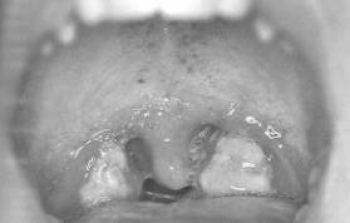

Boğaz İltihabı

Tıp dilinde farenjit veya anjin adı verilen bu hastalığın nedenleri; nezle ve grip gibi ateşli hastalıklarla, havadaki zararlı maddeler, sinüzit, alkol veya sigaradır.